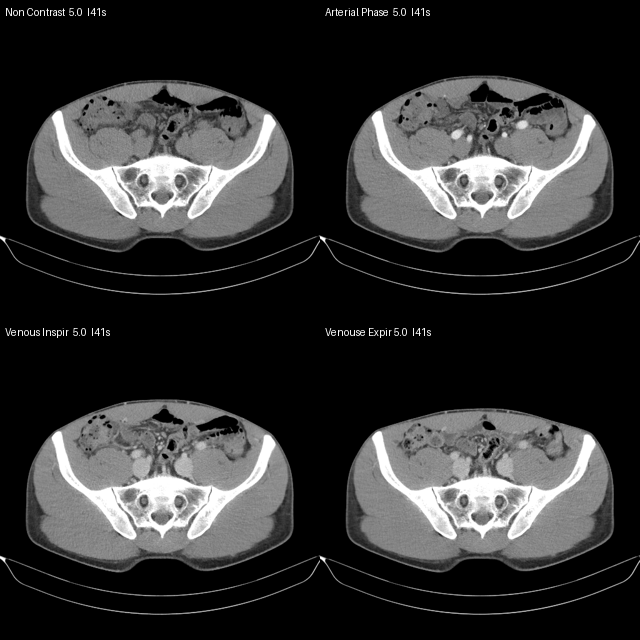

CT phase comparison: non-contrast, arterial, venous inspiratory, venous expiratory

central phase comparison: non-contrast, arterial, venous inspiratory, venous expiratory.